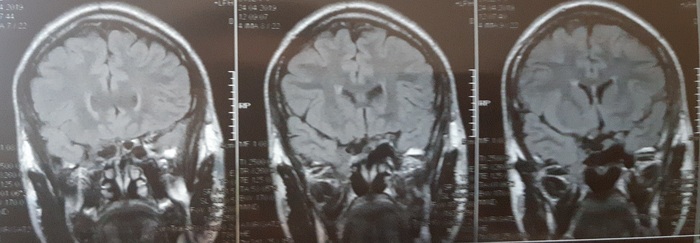

Сделал МРТ:

От вазотомии до аденомы гипофиза (пролактиномы). Часть 4

На этот раз описание очень подробное, аж страшно стало. Получается опухоль снова уменьшилась, но свободное пространство замещается лИкворной кистой. Нейрохирург сказал приходить на МРТ через год.